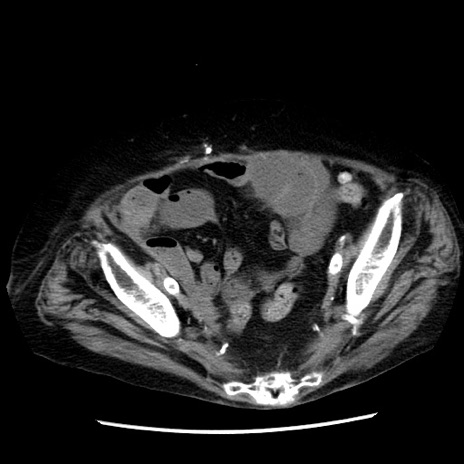

症例14(横断像)

【症例】 90歳代女性

【主訴】 腹痛・嘔吐

【現病歴】今朝から左側腹部痛を認めた。 経過観察していたが、嘔吐を認めたため来院。

【既往歴】 子宮癌術後

【身体所見】 意識清明、BP 127/54mmHg、P 98bpm Sp02 95%(RA)、BT 35.8°C、腹部平坦・軟腸ぜん動音聴取良好、右下腹部圧痛(+) 反跳痛なし

【データ】WBC 9800、CRP 0.46